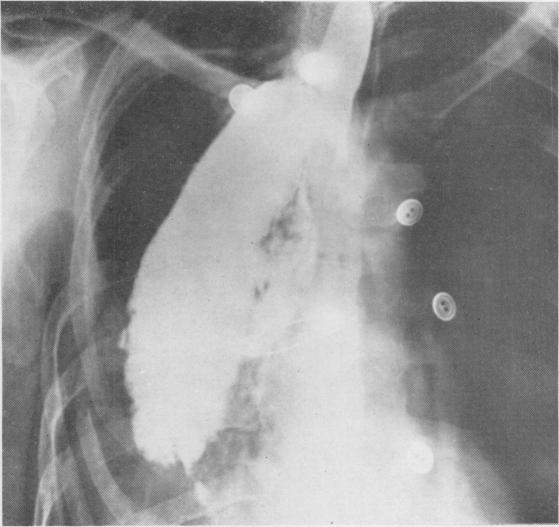

The present position of carcinoma of the oesophagus.

Postgrad Med J. 1947 Mar;23(257):109-39. doi: 10.1136/pgmj.23.257.109.